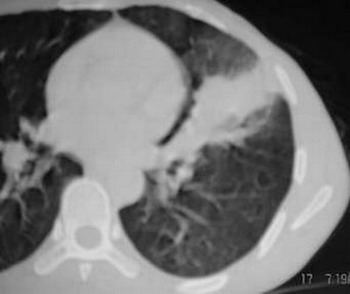

除大家上述征像外,左侧胸廓轻度内陷,纵隔影轻度左移,说明可能有肺不张,因而应首先考虑肿瘤的诊断。

左肺舌叶大片影,支气管通入,但有纠集,边界不清,与侧壁胸膜广基相续,首先考虑感染性病变.血象与血沉及痰检.除外有结核可能

左上叶下舌段肺不张,无明显强化,上叶下舌段支气管开口区见不规则狭窄,并见小结结灶,首先考虑支气管内膜结核并舌段肺不张,炎性假瘤不排除.